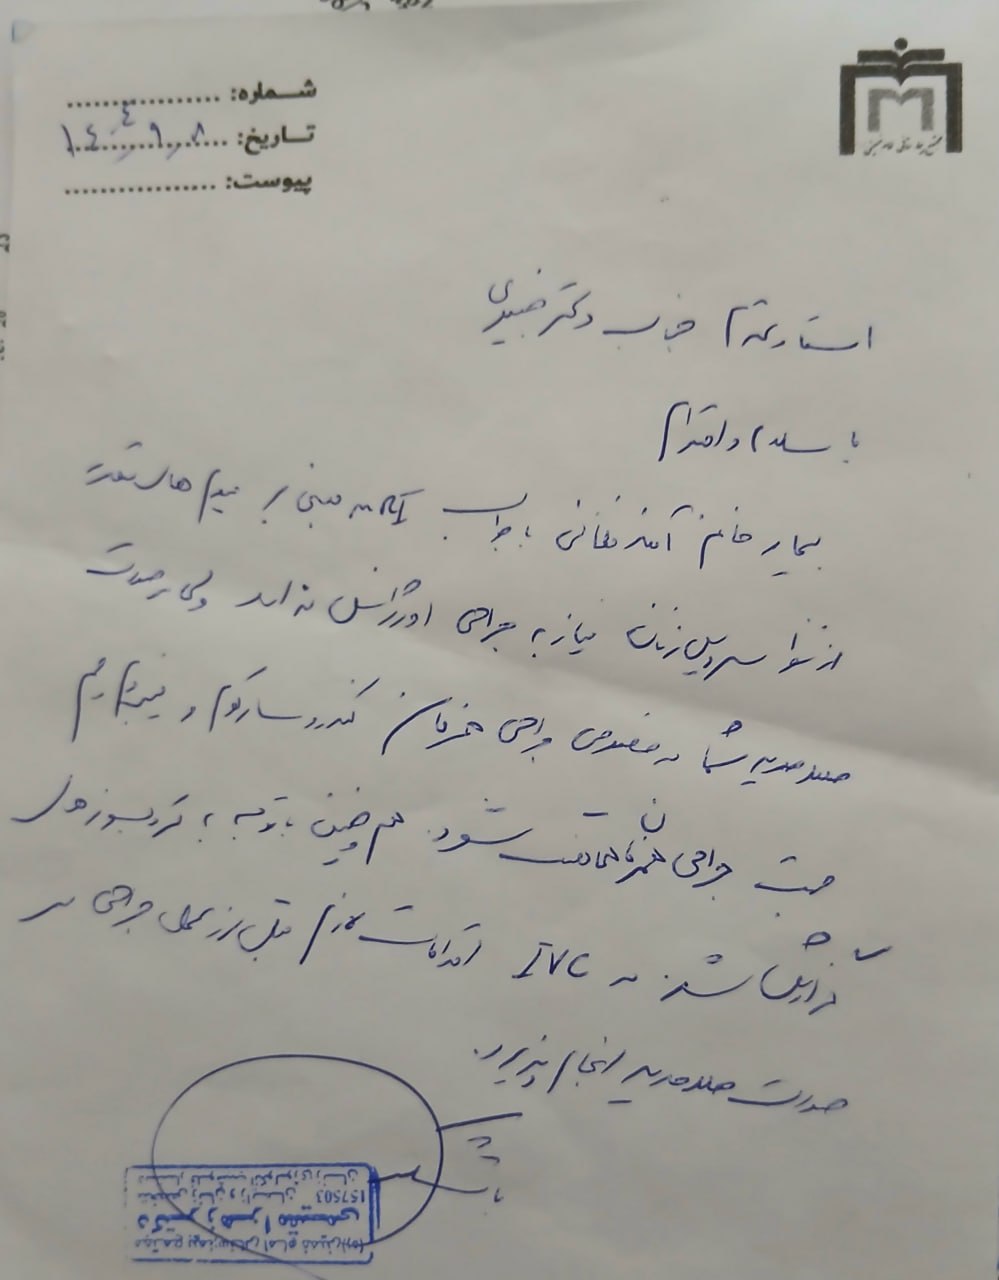

(تصویر مربوط به این مراجعه نیست) Other:

(تصویر مربوط به این مراجعه نیست) Other:

(تصویر مربوط به این مراجعه نیست) Other:

(تصویر مربوط به این مراجعه نیست) Other:

(تصویر مربوط به این مراجعه نیست) Other:

(تصویر مربوط به این مراجعه نیست) Other:

(تصویر مربوط به این مراجعه نیست) Other:

(تصویر مربوط به این مراجعه نیست) Other:

(تصویر مربوط به این مراجعه نیست) Other:

(تصویر مربوط به این مراجعه نیست) Other:

(تصویر مربوط به این مراجعه نیست) Other:

(تصویر مربوط به این مراجعه نیست) Other:

(تصویر مربوط به این مراجعه نیست) Other:

(تصویر مربوط به این مراجعه نیست) Other:

(تصویر مربوط به این مراجعه نیست) Other:

(تصویر مربوط به این مراجعه نیست) Other:

(تصویر مربوط به این مراجعه نیست) Other:

(تصویر مربوط به این مراجعه نیست) Other:

(تصویر مربوط به این مراجعه نیست) Other:

(تصویر مربوط به این مراجعه نیست) Other:

(تصویر مربوط به این مراجعه نیست) Other:

(تصویر مربوط به این مراجعه نیست) Other:

(تصویر مربوط به این مراجعه نیست) Other:

(تصویر مربوط به این مراجعه نیست) Other:

(تصویر مربوط به این مراجعه نیست) Other:

(تصویر مربوط به این مراجعه نیست) Other:

(تصویر مربوط به این مراجعه نیست) Other:

(تصویر مربوط به این مراجعه نیست) Other:

(تصویر مربوط به این مراجعه نیست) Other:

(تصویر مربوط به این مراجعه نیست) Other:

(تصویر مربوط به این مراجعه نیست) Other:

(تصویر مربوط به این مراجعه نیست) Other:

(تصویر مربوط به این مراجعه نیست) Other:

(تصویر مربوط به این مراجعه نیست) Other:

(تصویر مربوط به این مراجعه نیست) Other:

(تصویر مربوط به این مراجعه نیست) Other:

(تصویر مربوط به این مراجعه نیست) Other:

(تصویر مربوط به این مراجعه نیست) Other:

(تصویر مربوط به این مراجعه نیست) Other:

(تصویر مربوط به این مراجعه نیست) Other:

(تصویر مربوط به این مراجعه نیست) Other:

(تصویر مربوط به این مراجعه نیست) Other:

(تصویر مربوط به این مراجعه نیست) Other:

(تصویر مربوط به این مراجعه نیست) Other:

(تصویر مربوط به این مراجعه نیست) Other:

(تصویر مربوط به این مراجعه نیست) Other:

(تصویر مربوط به این مراجعه نیست) Other: